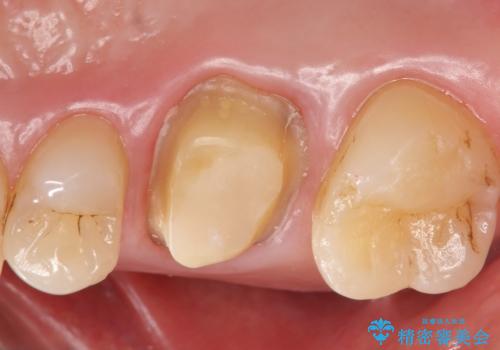

- 見た目が気になるため右上6のゴールドクラウンをセラミックにしたいといらっしゃった方の症例です。

再根管治療を御希望されたため根管治療を行った後、メタルボンドクラウンによる補綴を行いました。

- メタルボンドクラウン(エコノミー)…¥90,000、ファイバーコア…¥20,000、仮歯…¥10,000費用は治療当時の料金となります